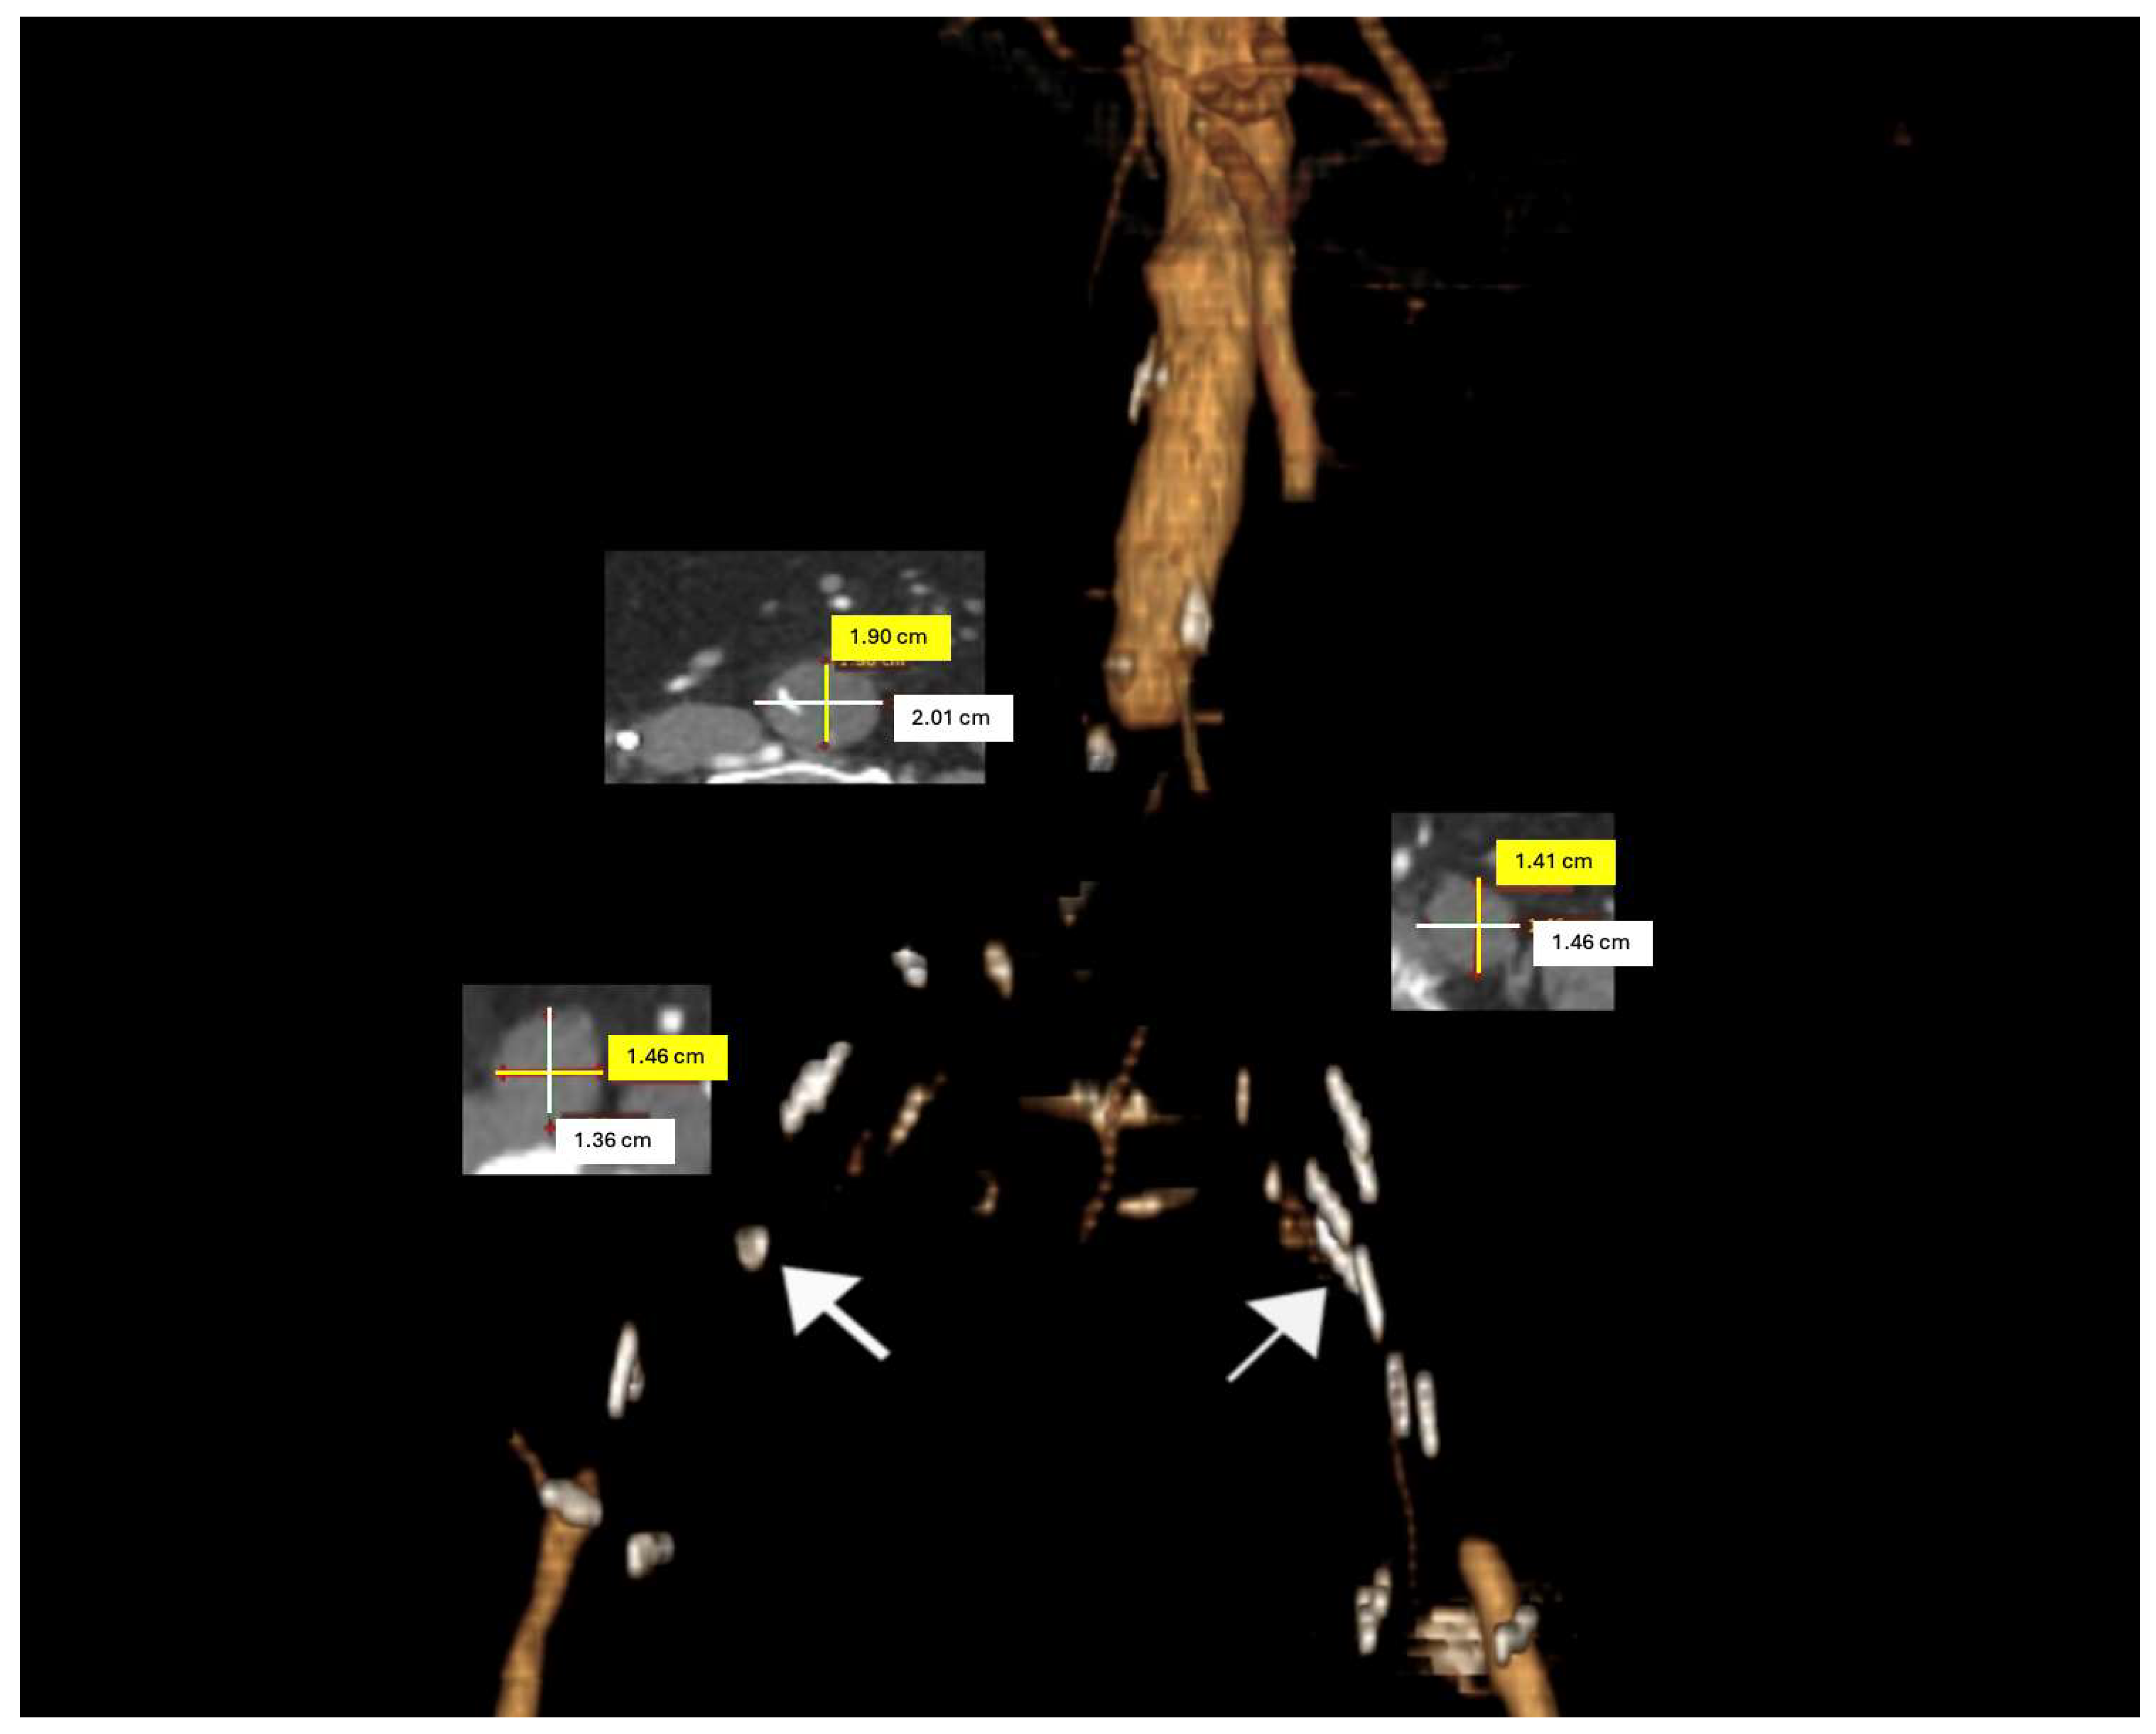

When the iliac lesion is complete, brachial access is also utilized for aortography. If the brachial artery diameter is adequate, a sheath is placed in the antecubital fossa using the Seldinger technique under ultrasound guidance. For sheaths larger than 6 Fr, access to the brachial artery is achieved via the cut-down technique. The lesion is crossed antegradely through the brachial access, and the guidewire is captured with a snare from the femoral artery to continue the procedure. If the common femoral artery is entirely occluded with no discernible lumen, an alternative approach involves creating retrograde access by initially performing an endarterectomy (Figure 2).

Figure 2. Intraoperative (a) and post-CERAB (b) aortography.